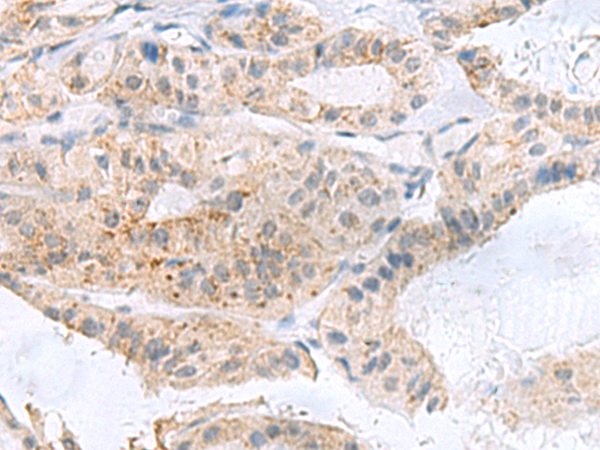

分类: 科研抗体货号: P10218别名: MSL1v2; C2orf67应用: IHC反应种属: Human, Mouse